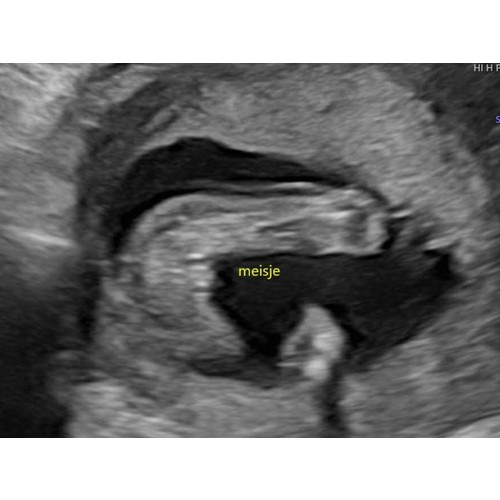

Zelf verwachten wij een meisje. Deze echo van is gemaakt met 17 weken